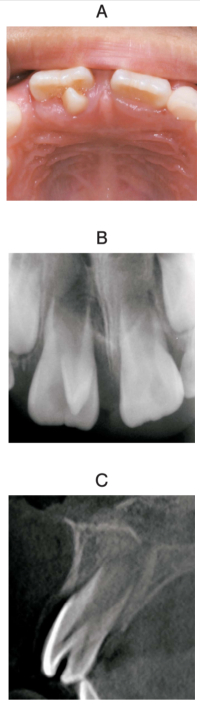

上顎右側中切歯の口腔内写真、エックス線画像及び歯科用コーンビーム CTを別に示す。この異常が発生する時期はどれか。1つ選べ。

b. 胎生6週〜胎生3か月